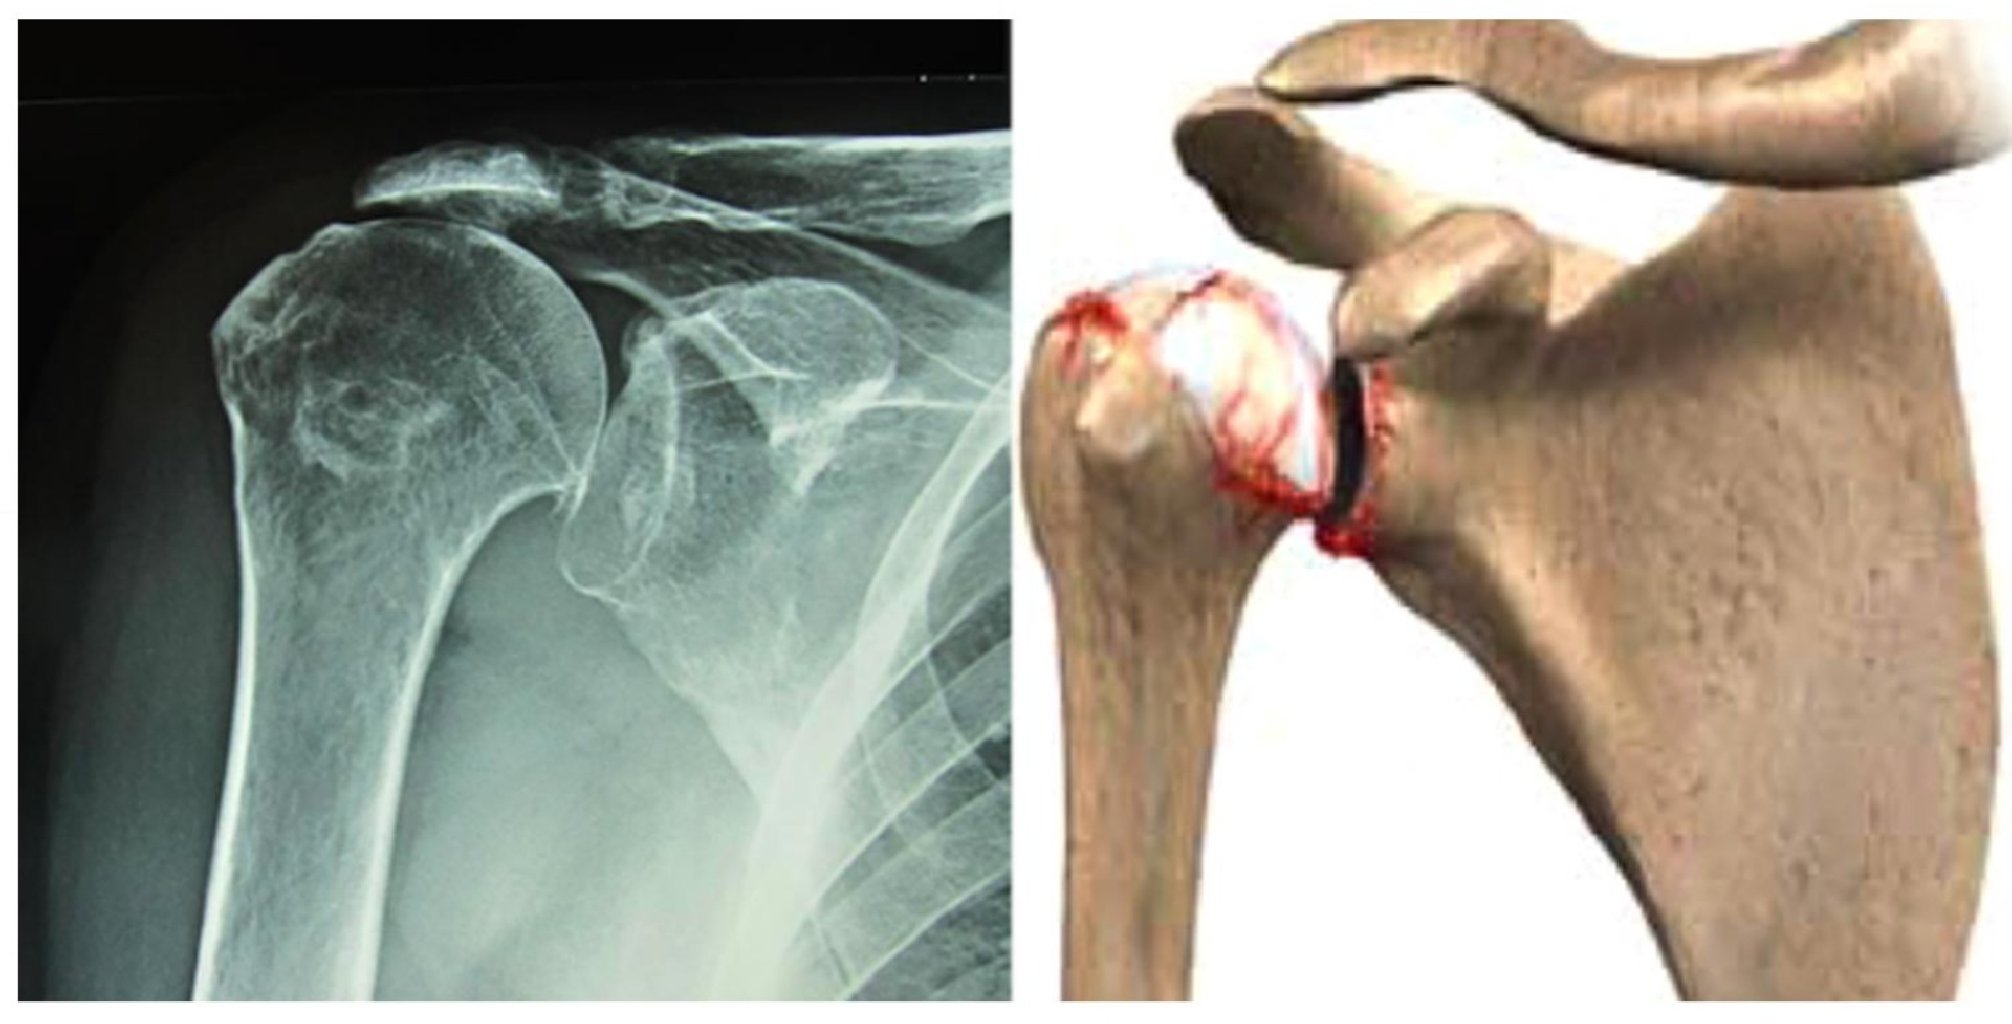

Səbəbləri Düşmələr: Əl üzərinə düşmə və ya birbaşa çiyinə düşmə. Yüksək sürətli travmalar: Avt ...